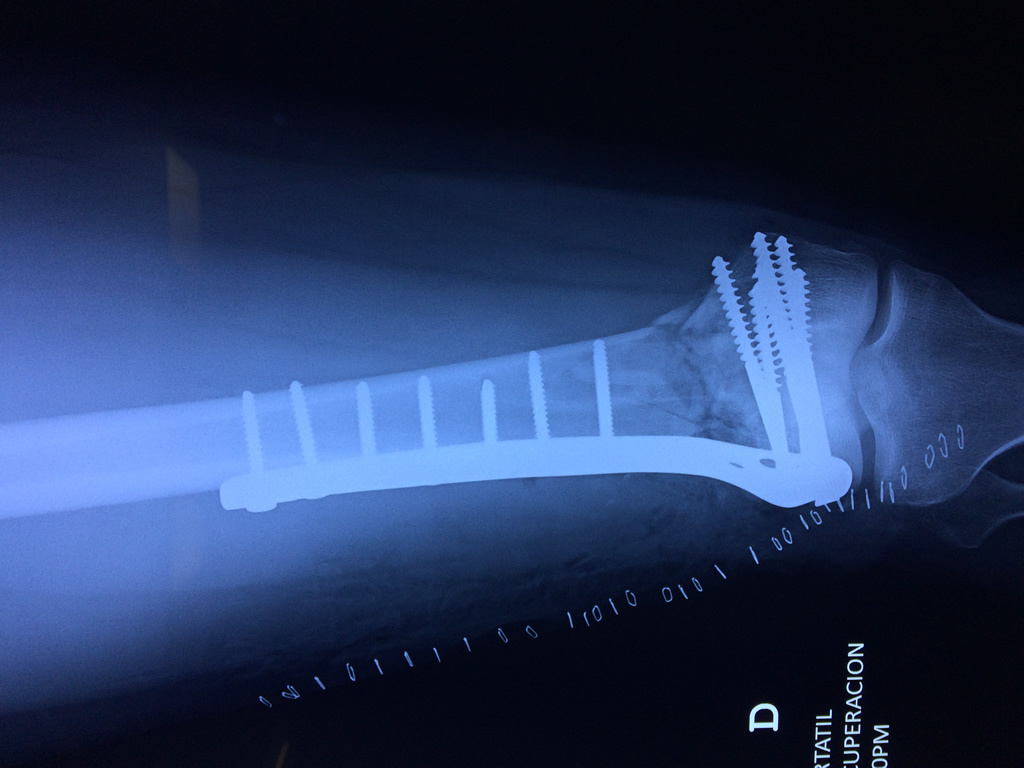

Cirugías de Húmero - Fémur

El fémur es el hueso del muslo, el segundo segmento del miembro inferior. Es el hueso más largo, fuerte y voluminoso del cuerpo humano.